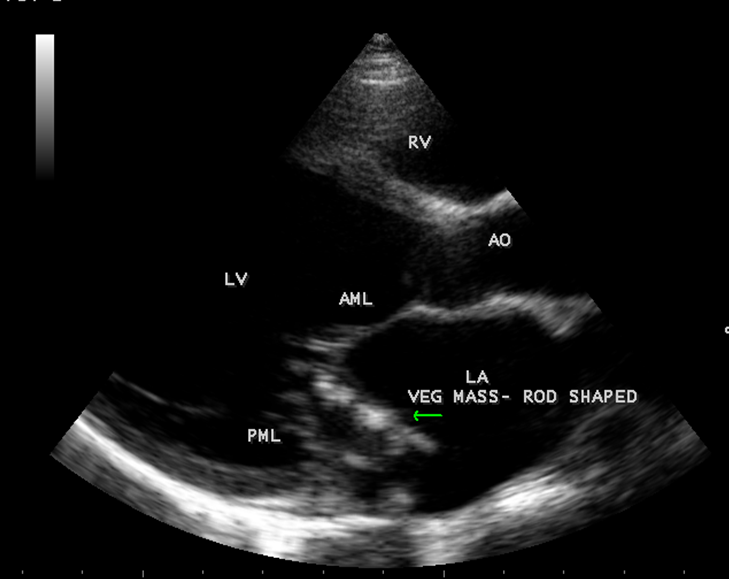

The most common and direct evidence of infective endocarditis is the vegetation and it begins as a microscopic focus of infection and gradually grows into a conspicuous mass. It is typically an irregularly shaped, highly mobile, echogenic mass attached to the free edge of a valve leaflet ( most commonly at the coaptation line) and tends to develop on the ‘upstream’ side of the valve leaflets ( ie, the ventricular side of aortic valve and the atrial side of mitral and tricuspid valves. They may be seesile or pedunculated, but usually has an oscillating or fluttering motion, a typical feature of most vegetations. Vegetation move with the leaflet in a more chaotic (‘oscillating’) manner and it may prolapse through the valve into the LV (left ventricle) as it opens as shown in Figures 3, 4 and 16 and into LA (left atrium) as it closing (Figure 5 and 6) . The mass of vegetation is typically homogeneous with echogenicity similar to that of the myocardium. The infectious process often alter the valvular structure and function. Extensive involvement of the leaflet may result in chordal rupture, leading to severe regurgitation as shown in Figure 21 . Direct and typical signs of RMCT (ruptured mitral chordate tendineae) were chain-flail or whiplash-like changes and had an incidence of 86.7%, causing severe regurgitation and mitral chordal rupture is the leading cause of flail mitral leaflet[30]. A large vegetation may obstruct the valve orifice as shown in Figure 1 and 2 , sometimes termed as “obstructive-type bacterial endocarditis” and producing a functional valve stenosis ( Ping-Pong mitral stenosis [31]) similar to left atrial myxoma as shown in Figure 29.

The shape and size of vegetation are quite variable and mostly it is polypoid [32]. The typical vegetation is a ‘sessile’ or ‘ pedunculating’ valve – attached mass. A ‘sessile’ vegetation had to be completely attached to the valve as shown in Figures 34 and 35 in a 63- year old male, in which a large vegetation is attached to the atrial side of anterior mitral leaflet [33-Figure 13.3-A], producing severe mitral regurgitation as shown in Figure 36 and a mobile vegetation showed a pedunculating part prolapsing into the ventricle as shown in Figure 3 and 4 or atrium as shown in Figure 5 [33-Figure 13.1] in a 10-year old female child. A vegetation was considered as ‘definite’ when shaggy echoes in the M-mode study as shown in Figure 20 . and a corresponding mass without restricted valve motion in the two-dimensional echocardiogram were found as shown in Figure 16 and 30 [33-Figure 13.7]. The vegetation vary in size, often being just a few mm and sometimes reaching to 2-3 cm. A vegetation must be atleast 3 to 6 mm in size to be reliably seen. The mean size of vegetation was 0.6 mm (range 3 to 28) and vegetation > 10 mm in diameter was defined as ‘large’ and those ≤ 10 mm in diameter was defined as ‘small’ and ≥ 15 mm is ‘very large’. Vegetations resulting from fungal infections (candida, aspergillus) are usually much bigger than bacterial vegetations and can be so big to be mistaken for a cardiac tumor. The large vegetations are at increased risk for embolic complications [34], especially on the anterior leaflet of the mitral valve with mobility [35]. A vegetation size of 3.2 x 4.4 cm is called as ‘giant vegetation’ on the mitral valve with a fibrillary appearance of the mass [36- Figure 3] as shown in Figure 1 is an important predictor of embolic phenomena in patients with infective endocarditis causing severe mitral regurgitation as ‘Duck’ shaped jets (Figures 24 and 25 ), disorganized (Figure 21) and sometimes the regurigitant jet splits into two components as one into LA and the second one into LV simultaneously as a bileaflet jets (Figure 10 ) similar to bileaflet structure of AML with vegetation masses (Figure 9 ) . The size of the largest vegetation reported on the mitral valve in the literature in patients with bacterial endocarditis is 7x4 cm[37]. In a study of Nunes, et al[38], vegetation size >13 mm was the only independent predictor of mortality, but some studies [39],[40] did not had an increased embolic risk in patients with vegetation focused only on its presence and size and not on their location. Embolic complications may occur in infective endocarditis(20.6%)and were not more prevalent in the groups with large vegetations [41]. However, Wong, et al [42] found an increased need for surgery in patients with a large vegetation (>10 mm).

The shape of vegetation varies in this child as ‘popcorn’ like (Figures 1,3 and 4 ), rod-shaped (Figure ), basket shaped (Figure 7 )[33-Figure 13.3], ‘baby in hand’ appearance (Figure 18), ‘cucumber shaped (Figure 2 ) and a ‘bunch of plantain’appearance (Figure 33 ), ring shaped (Figure 19 }, bileaflet structure (Figure 9 )with bileaflet MR jet as shown in Figure 10 . and kissing forms (Figure 13 - parasternal long axis view, Figure 14 - apical four chamber view and Figure 15 - short axis view)